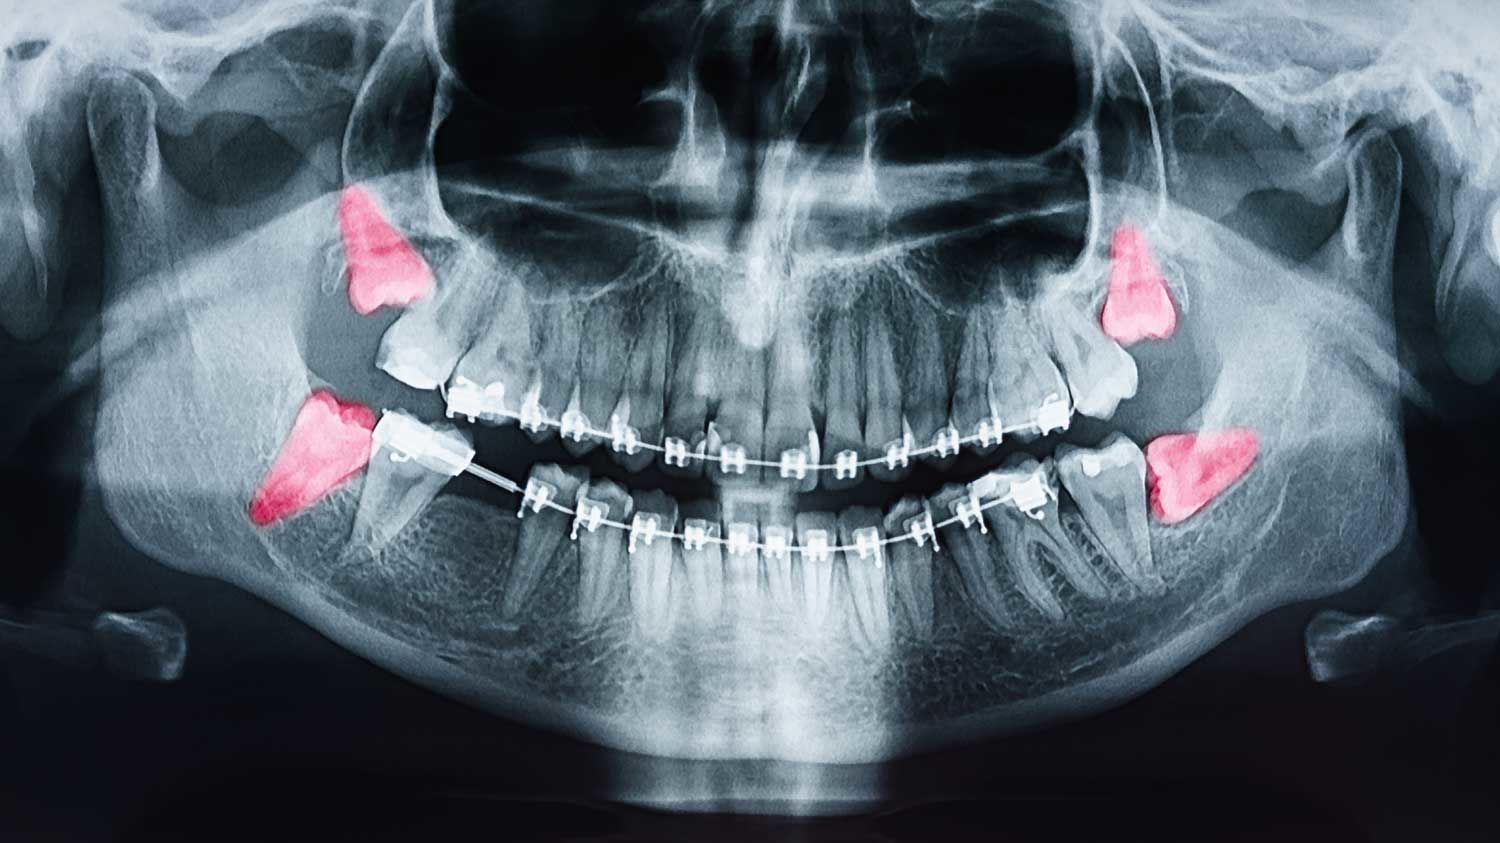

When Should I Extract Impacted Wisdom Teeth - Woodbridge Dentists

The Different Types Of Impacted Wisdom Teeth Explained By Your General Family Dentist In Portland